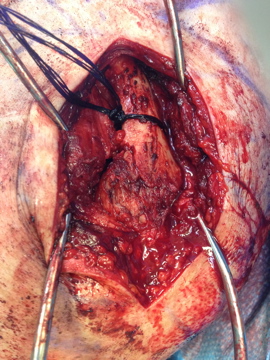

There was a picture taken of my shoulder during the operation (after the surgeon tied my clavicle down and before the plate was screwed on). I’ll warn you that it’s pretty raw so if you don’t like looking at blood and open wounds don’t click… Operation pic. If you look closely you can see the fracture.